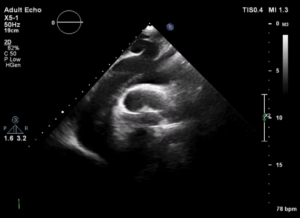

2.主动脉瓣病变

当马凡综合征患者主动脉根部扩张时,往往导致主动瓣膜的关闭不全,而此时可能瓣膜本身发育是良好的,当手术纠正主动脉根部的病变时,主动脉瓣膜的关闭不全可能随之得到改善甚至消失(图14.15);而当主动脉瓣叶本身有发育异常的时候,伴随中、大量的反流,可能随之会导致主动脉根部及升主动脉的病变,从而增加主动脉夹层发生的概率。

这时候,超声的随访与评估就显得尤为重要,经胸超声心动可对主动脉瓣叶的形态,活动、启闭、瓣环、窦部、瓣膜是否有反流及反流程度进行评估(图16.17),早发现,早治疗,对预防马凡综合征患者引发主动脉夹层有着重要的意义。

图16.对主动脉瓣环进行测量

图17.评估窦部及瓣叶情况